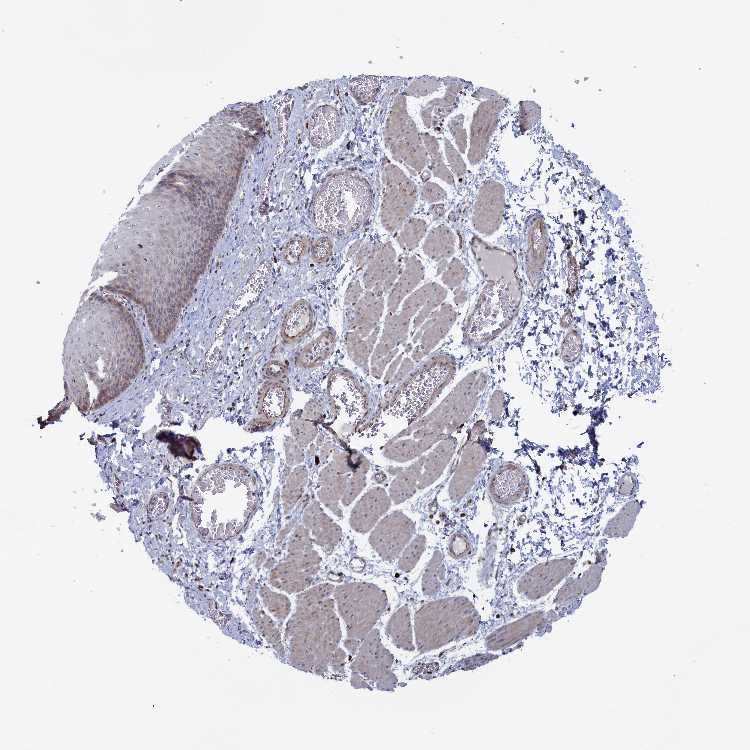

ESOPHAGUS - Antibody stainingi

Antibody staining in the annotated cell types in the current human tissue is reported as not detected, low, medium, or high, based on conventional immunohistochemistry profiling in selected tissues. This score is based on the combination of the staining intensity and fraction of stained cells.

Each image is clickable and will lead to virtual microscopy that enables deeper exploration of all samples and also displays staining intensity scores, fraction scores and subcellular localization as well as patient and tissue information for each sample.

Antibody HPA040915Antibody HPA040956

Squamous epithelial cells Not detectedLow